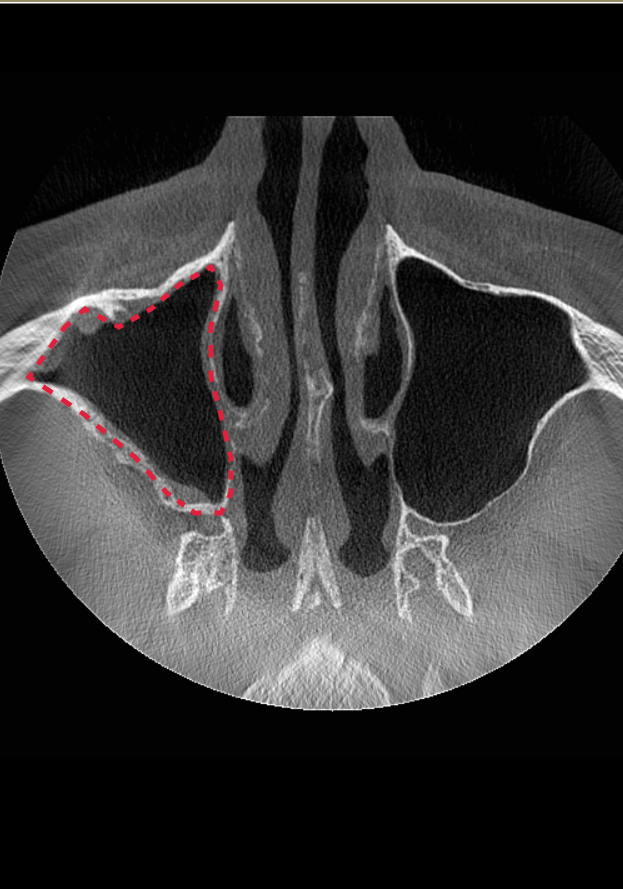

Компьютерная томография после ЛОР-лечения. Синус-лифтинг проводить можно.